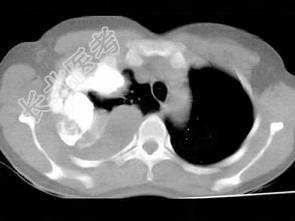

- 单项选择题男,66岁, 剧烈胸痛,请结合CT图像, 选择最可能的诊断 ( )

A、右侧胸腔积液胸膜钙化

B、右肺癌侵犯胸膜

C、右侧胸膜间皮瘤

D、右侧肺不张

E、右侧肺肺癌